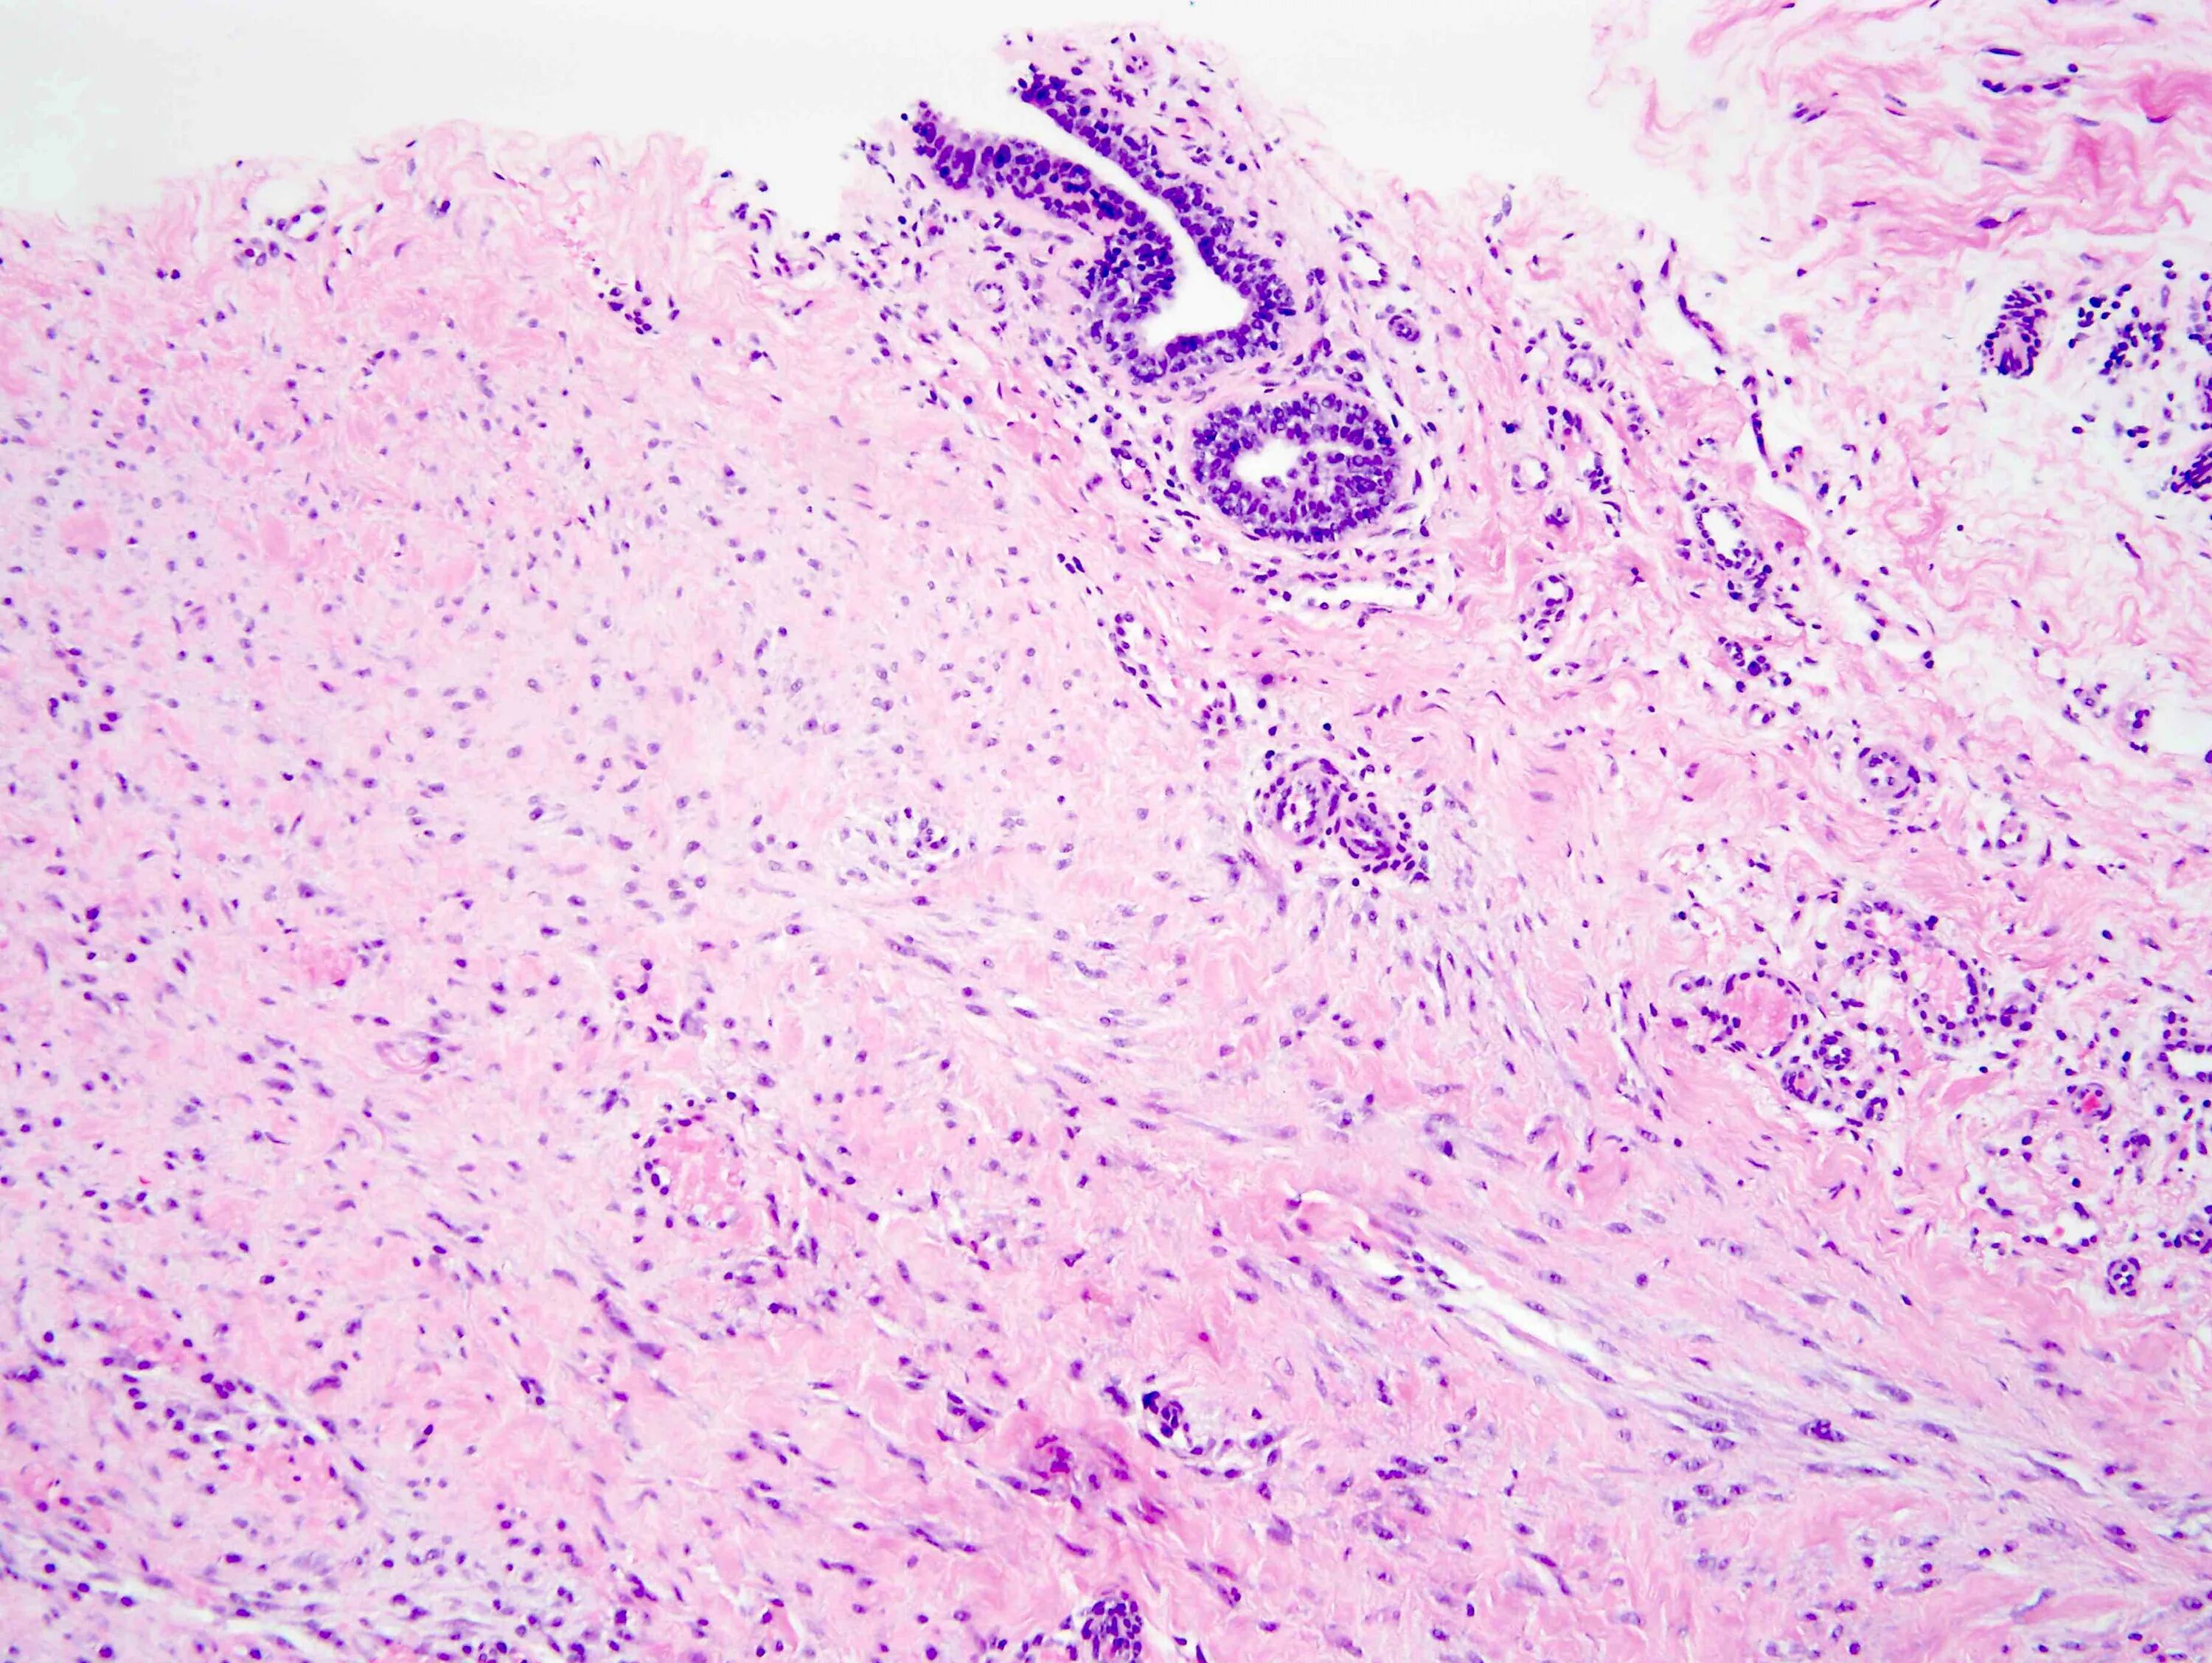

Фиброматоз мягких